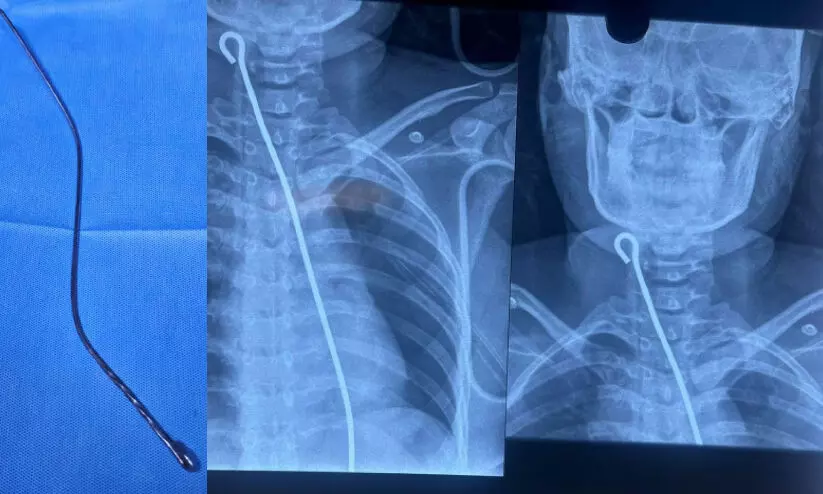

text_fields1. പപ്പടക്കോൽ പുറത്തെടുത്തതിനുശേഷമുള്ള ചിത്രം, 2. പപ്പടക്കോൽ വിഴുങ്ങിയതിന്റെ എക്സ്റേ

മലപ്പുറം സ്വദേശിനി അബദ്ധത്തിൽ വിഴുങ്ങിയത് നീണ്ട ഒരു പപ്പടക്കോലായിരുന്നു. വളരെ പ്രശസ്തമായ സ്വകാര്യ ആശുപത്രികൾപോലും കൈവെടിഞ്ഞപ്പോഴാണ് 33കാരിയുമായി ഭർത്താവ് മെഡിക്കൽ കോളജിലെത്തിയത്. എക്സ് റേയിൽ പപ്പടക്കമ്പി വളരെ വ്യക്തമായിരുന്നു. അന്നനാളത്തിലൂടെ പോയി ഇടതു ശ്വാസ കോശം തുരന്ന് ആമാശയത്തിൽ ഉറച്ചു നിൽക്കുകയായിരുന്നു ലോഹത്തിൽ തീർത്ത പപ്പടക്കമ്പി.

ഓപറേഷൻ ചെയ്യുകയാണെങ്കിൽ അതിസങ്കീർണമാണ് കാര്യങ്ങളെന്ന് എല്ലാവർക്കും ബോധ്യമായിരുന്നു. ഹൃദയമടക്കമുള്ള അവയവങ്ങൾ മുഴുവനായും തുറന്നുമാത്രമേ കോൽ പുറത്തെടുക്കാനാവൂ. വിജയസാധ്യതയാണെങ്കിൽ തീരെ കുറവ്. ഈ അവസ്ഥയിലാണ് മെഡിക്കൽ കോളജിലെ വിവിധ വിഭാഗങ്ങളിലെ ഡോക്ടർമാർ ഒന്നിച്ചുചേർന്ന് വായിൽക്കൂടി തന്നെ കോൽ വലിച്ചെടുക്കാനുള്ള സാധ്യതയെക്കുറിച്ച് ചിന്തിച്ചത്. ഇ.എൻ.ടി, അനസ്തേഷ്യ, കാർഡിയോ തൊറാസിക് സർജറി, ജനറൽ സർജറി വിഭാഗങ്ങളിലെ ഡോക്ടർമാരുടെ കഠിനാധ്വാനവും സമയോചിതമായ ഇടപെടലും മൂലം വലിയ പരിക്കുകൾ കൂടാതെ പപ്പടക്കോൽ വായിലൂടെ തന്നെ വലിച്ചെടുക്കാൻ സാധിച്ചു.

‘‘ഭാഗ്യം തുണച്ചു എന്നത് നേരാണ്. എന്നാൽ, ഡോക്ടർമാരുടെ കൂട്ടായ പ്രവർത്തനവും മെഡിക്കൽ കോളജിലെ ആധുനിക ഉപകരണങ്ങളും കൂടിയാണ് സംരംഭം വിജയത്തിലെത്തിച്ചത്’’ -ഡോ. ഫിജുൽ കോമു പറഞ്ഞു. ഏത് നിമിഷവും ഹൃദയം തുറന്നുള്ള ഓപറേഷൻ വേണ്ടിവരാം എന്നുള്ളതുകൊണ്ടുതന്നെ അതിനുള്ള എല്ലാ സൗകര്യങ്ങളും ഒരുക്കിയതിനു ശേഷമായിരുന്നു രോഗിയെ ബോധംകെടുത്തി കമ്പി പുറത്തെടുക്കാൻ ശ്രമിച്ചത്. ഏതു സമയത്തും ലോഹക്കമ്പി പൊട്ടിപ്പോകാനും ഏതെങ്കിലും ആന്തരികാവയവങ്ങളിൽ കമ്പിയുടെ കൂർത്ത ഭാഗം തട്ടി രക്തസ്രാവം ഉണ്ടാകാനും സാധ്യതയുണ്ടായിരുന്നു. ഫൈബർ ഒപ്റ്റിക് ഇൻടുബേറ്റിങ് വിഡിയോ എൻഡോസ്കോപ്, ഡയറക്ട് ലാറിങ്നോസ്കോപി എന്നീ ആധുനിക ഉപകരണങ്ങളാണ് ഈ സമയം ഡോക്ടർമാരുടെ രക്ഷക്കെത്തിയത്. ഐ.സി.യുവിൽ യുവതി ഇപ്പോൾ സുഖം പ്രാപിച്ചുവരുകയാണ്.